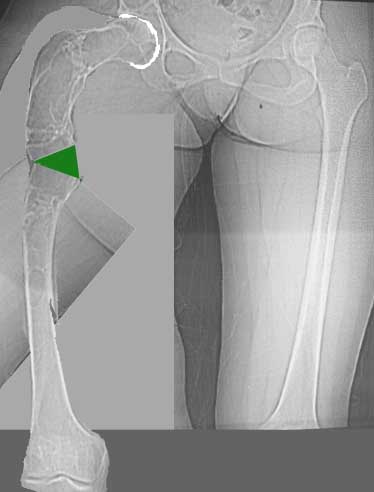

Моё мнение, что двойная остеотомия бедра с аппаратом Илизарова + Гексаподный механизм, или Тэйлора, В данной ситуации является методом выбора. Я очень извеняюсь за качество прилагаемых снимков, в которых я постарался отразить разницу междe одной и двумя остеотомиями бедра.

jo> отразить разницу межде одной и двумя остеотомиями бедра.

Скорее всего, второй уровень может оказаться нелишним лишь при переходе с аппарата на интрамедуллярный стержень. И его не поздно будет пересечь именно в момент введения гвоздя, если будет угроза перфорации стенки канала.

Если сделать фото больного после устранения деформации, вряд ли удастся догадаться, на скольких уровнях она устранялась.